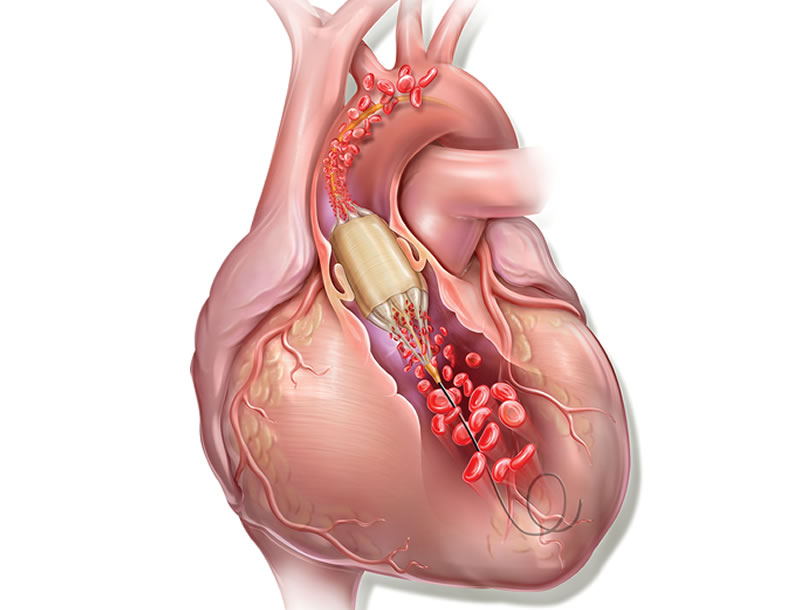

La valvuloplastia aórtica con balón exige la estimulación cardiaca rápida mediante marcapasos para evitar que el globo se mueva durante el inflado y pueda causar daño en los velos o incluso en el anillo al deslizarse de forma incontrolada. Por otra parte, cuando hacemos una valvuloplastia, el inflado del balón (que dura 5 s aproximadamente) provoca la obstrucción del flujo en el tracto de salida del ventrículo izquierdo e isquemia, que en algunos enfermos puede condicionar un deterioro importante de su situación hemodinámica.

True Flow (Bard, EEUU) es un balón de valvuloplastia que permite el flujo a su través mientras está inflado. Su recubrimiento exterior está compuesto por un tejido de fibras que evita el deslizamiento del balón al abrirse sobre los velos valvulares, por lo que no se necesita estimular el corazón con marcapasos. Este tejido esta formado por poliuretano de alto peso molecular, poliéster y fibras de aramida (componente estructural del Kevlar) que posee una baja distensibilidad y alta resistencia a la rotura. El interior del balón tiene 8 globos de pequeño diámetro en el perímetro del balón principal, y deja un espacio entre ellos por donde fluye la sangre. El dispositivo mide 3,5 cm de largo y está disponible en seis tamaños, con diámetros que van de los 18 a los 26 mm. Los más pequeños son compatibles con un introductor de 11 French y el más grande con introductor de 16 French.

Este tipo de balón permite realizar la valvuloplastia durante 60 s o incluso más sin estimulación rápida, con una disminución de 1/3 de la presión media aórtica durante el inflado, lo que garantiza reducciones del 50% en el gradiente aórtico. Algo de gran utilidad cuando los enfermos tienen una disfunción grave.